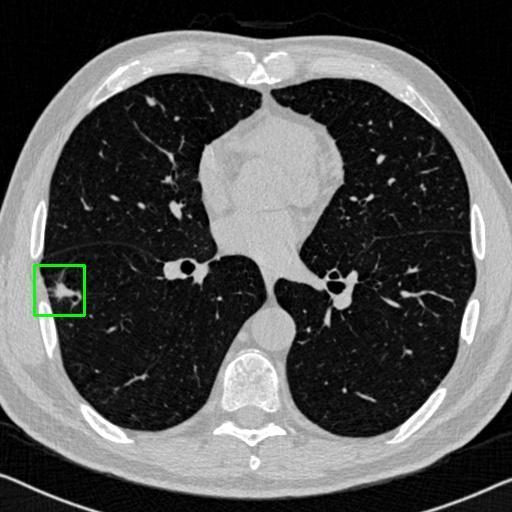

We developed an AI-based system using deep learning models for analyzing lung CT scans to detect and classify pulmonary nodules. We chose the YOLOv11 architecture for its enhanced object detection capability and adapted it specifically for medical imaging, incorporating pixel-level precision and severity classification.

Classification into three severity levels with colored bounding boxes.

Successfully built and deployed an AI model (YOLOv11) capable of detecting lung nodules in CT scans with high accuracy and real-time performance.

Designed a severity classification system that categorizes nodules into null, moderate, and severe using colored bounding boxes, assisting in rapid clinical decision-making.